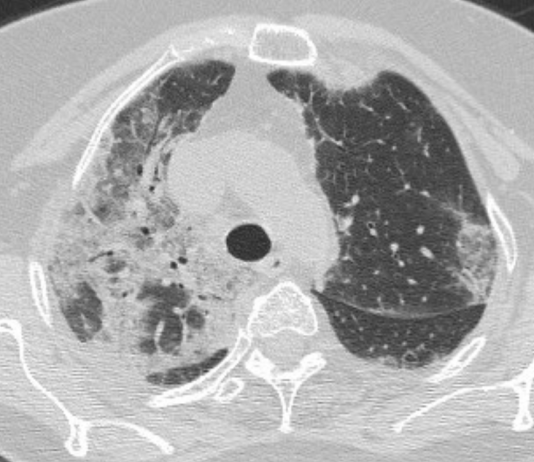

Maschio, 66 anni. In anamnesi: diabete mellito; ipertensione arteriosa;...